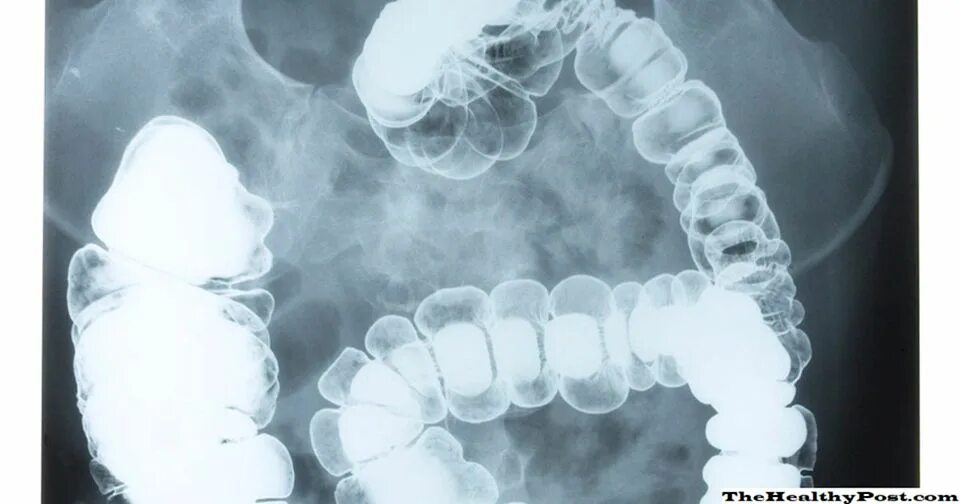

Атония кишечника симптомы у пожилых лечение